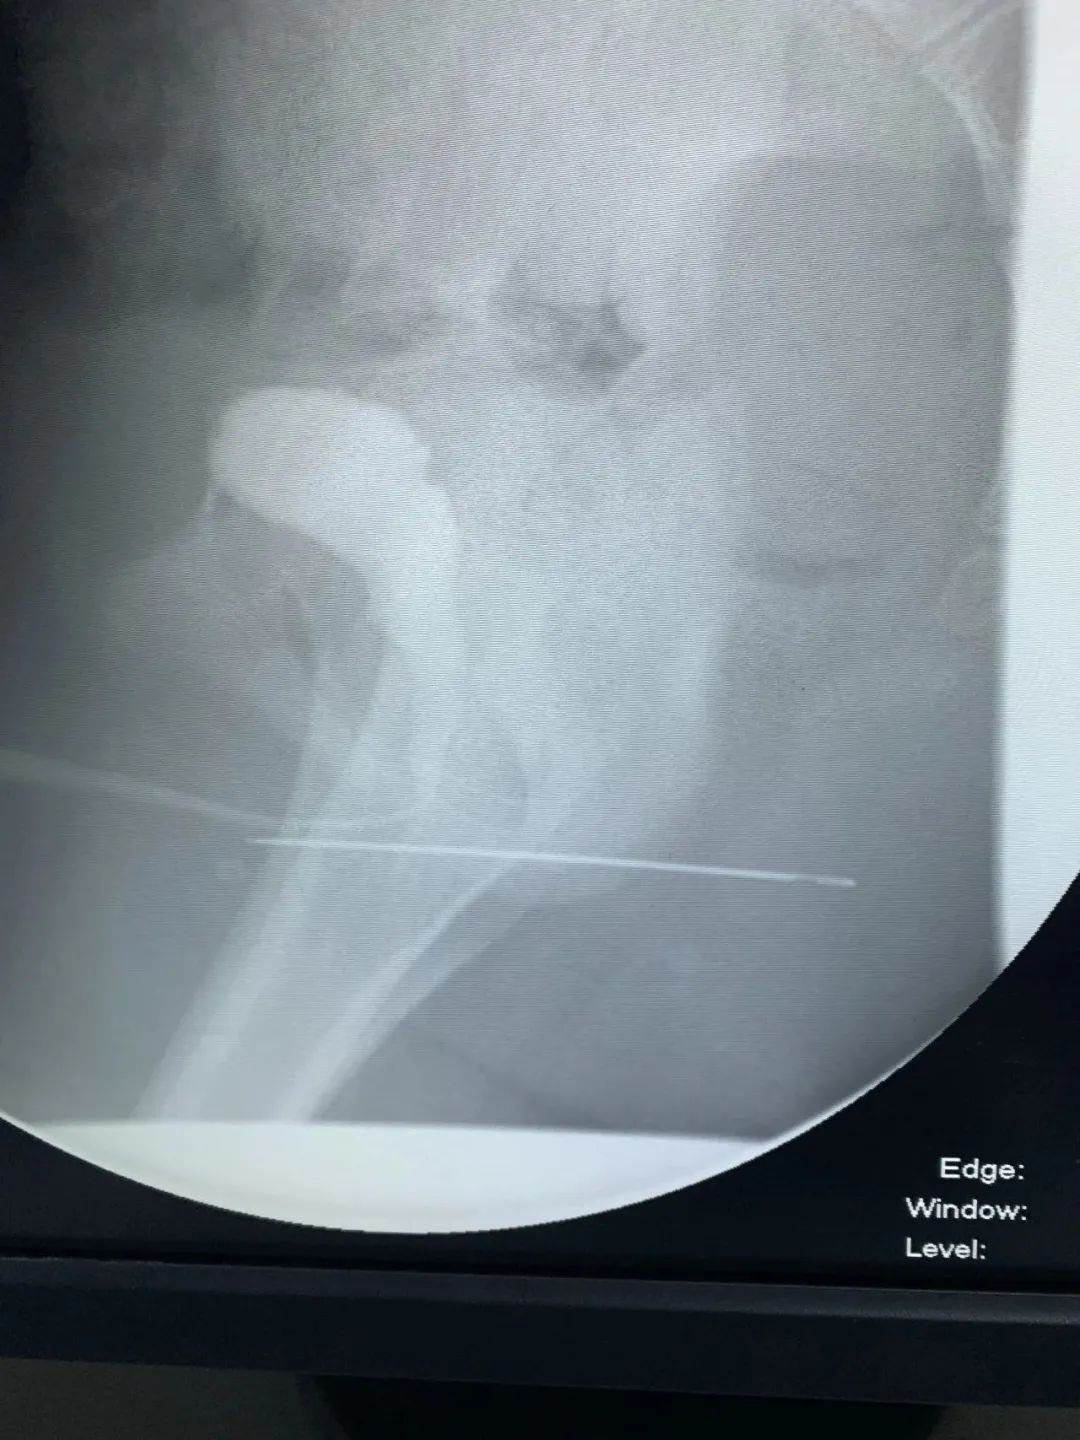

在CT影像画面中,金金的膀胱内发出一阵闪亮的强光,明显意味着金金的体内存在着金属物。接诊医生根据以往的看诊经验和CT影像金属物的形状,初步判定孩子膀胱里的极有可能是一串磁力珠。好端端的,磁力珠是怎么进入孩子膀胱的?

当务之急就是立即将孩子体内的磁力珠取出。当天,金金在浙大儿院进行了微创手术。泌尿外科王恒友医生在尿道膀胱镜的监测下,在金金的肚子上开了一个近10毫米的小孔,通过腹壁建立通往膀胱的通道后,利用金属夹成功将金金体内的磁力珠全部取出,共计55颗!被塞进尿道的还有掏耳勺、长针等